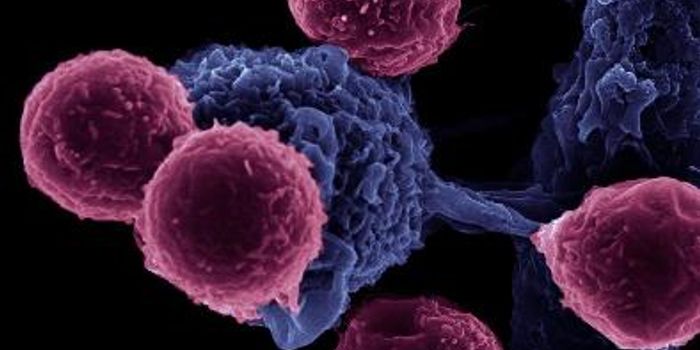

JUN 26, 2015CancerOne reason why cancer is so harmful is that it can trick "checkpoint" proteins found on the immune system's T cells, vir ...

APR 15, 2015CancerThe human immune system is poised to spring into action at the first sign of a foreign invader, but it often fails to el ...